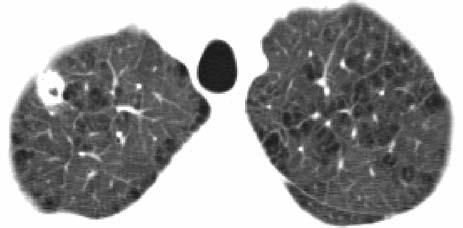

Laboratory evaluation revealed a normal complete blood cell count but mildly elevated levels of transaminases. A chest radiograph revealed a 2-cm cavitary right upper lobe (RUL) lesion (Figure 1). CT scans of the chest and abdomen revealed the solitary lung lesion, on a background of centrilobular emphysema (Figure 2), and bilateral non-homogeneous adrenal glands, with the left gland appearing larger than the right one (Figure 3). CT scans did not reveal any mediastinal lymphadenopathy or pleural effusions.

Figure 2 – A 2-cm thick-walled cavitary lesion in the right upper lobe, on a background of emphysema, is revealed in this chest CT scan (5-mm axial cuts, lung window setting).